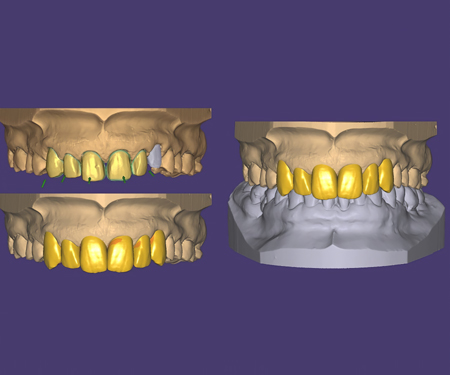

全瓷修复

美学修复